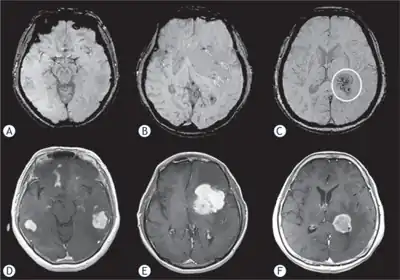

Brain magnetic resonance imaging showing primary central nervous system B-cell non-Hodgkin lymphoma of the sella turcica and hypothalamus, continuing to the tectum (intensely white areas in the middle).

MRI or contrast enhanced CT classically shows multiple ring-enhancing lesions in the deep white matter. The major differential diagnosis (based on imaging) is cerebral toxoplasmosis, which is also prevalent in AIDS patients and also presents with a ring-enhanced lesion, although toxoplasmosis generally presents with more lesions and the contrast enhancement is typically more pronounced. Imaging techniques cannot distinguish the two conditions with certainty, and cannot exclude other diagnoses. Thus, patients undergo a brain biopsy or vitreous biopsy, if there is intraocular involvement.[11]